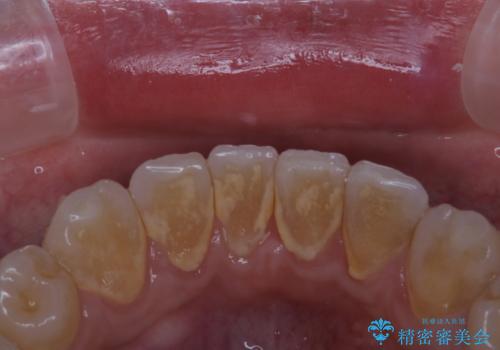

- インビザラインでのマウスピース矯正中の患者様です。

歯石による舌ざわりが気になるとのことでした。

PMTC30分コースを行いました。

プラークやバイオフィルムといった細菌などを放置すると歯石となります。歯石になってしまうと歯磨きでは取り除くことができないため、歯科医院にて専門的な機械や材料を使用してクリーニングを受ける必要があります。